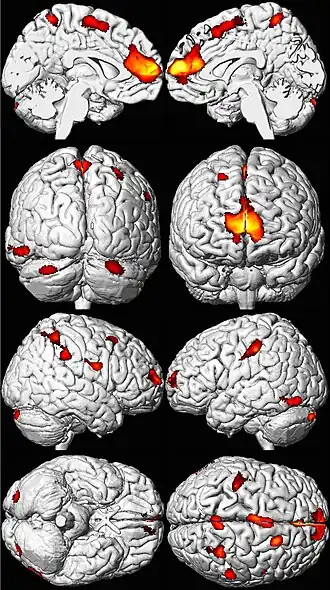

Les zones de perte de volume cérébral apparaissent ici en couleur sur un modèle de cerveau normal[201].